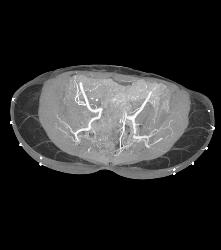

Sgap Flap Planning to Define Gluteal Arteries